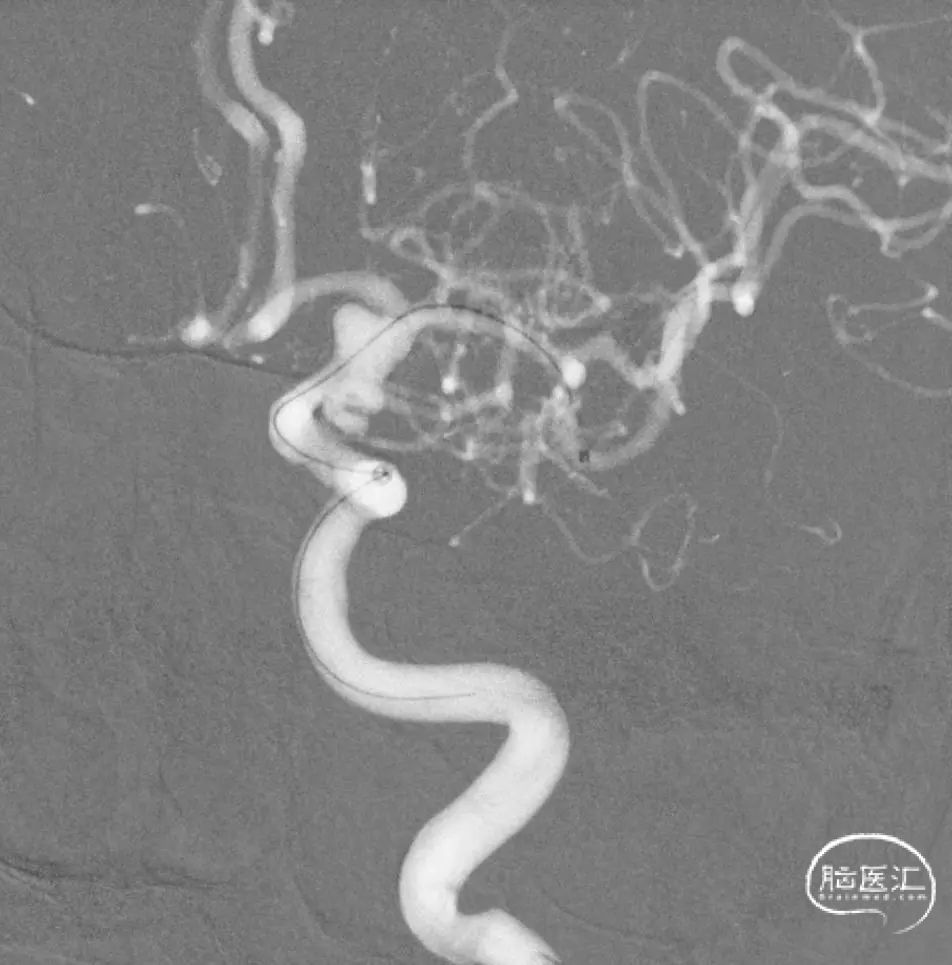

正侧位及旋转造影见动脉瘤栓塞满意。

术后CT: